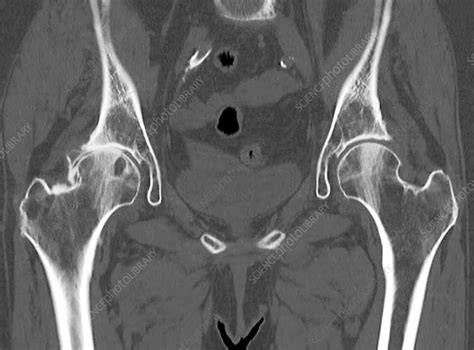

Alright, let’s get down to brass tacks: what is a bone-stock hip CT scan, anyway? Think of it as a super-detailed X-ray, but instead of just one snapshot, a CT (Computed Tomography) scan uses multiple X-ray beams from different angles to create cross-sectional images, or slices, of your hip bone and the surrounding structures. The “bone-stock” part is key here. While a standard hip CT might look at soft tissues too, a bone-stock CT specifically focuses on the bone itself. We’re talking about the intricate details of your femur (thigh bone), the acetabulum (the socket in your pelvis), ligaments, cartilage, and any other bony landmarks. It’s like having a 3D model of your hip, built entirely from bone data. This is crucial because many hip problems stem from issues with the bone structure – think arthritis wearing away the cartilage and bone, fractures from injuries, or developmental abnormalities. Doctors use this scan to get an incredibly precise view of the bone’s shape, density, and integrity. It helps them see things that a regular X-ray might miss, like tiny hairline fractures or subtle changes in bone alignment. So, when your doctor mentions a “bone-stock hip CT,” they’re essentially asking for a high-resolution, bone-centric look at your hip joint to pinpoint problems with the underlying skeletal structure. It’s a powerful tool for diagnosis and treatment planning, giving your medical team the granular detail they need to make the best decisions for your hip health. We’re not just looking at a blurry shadow; we’re examining the very architecture of your hip joint in remarkable detail. This level of clarity is what makes it so valuable in orthopedic care, guys. It’s all about getting to the root of the issue by examining the boney foundation of your hip.

Okay, you’ve had your bone-stock hip CT , and now you’re waiting for the results. What can you expect when your doctor sits down with you to discuss the report? It can feel a bit overwhelming with all the medical jargon, but let’s break down some of the key things the radiologist will be looking for and what they might mean for you. The report will essentially describe the anatomy of your hip joint in detail, focusing on the bony structures. They’ll examine the acetabulum , which is the socket part of your hip. They’ll note its shape, depth, and whether there are any signs of wear, damage, or abnormalities like flattening or irregularity, which are common in hip dysplasia or advanced arthritis. Next, they’ll look at the femoral head , the ‘ball’ part of your hip joint that sits in the socket. They’ll assess its shape, size, and how well it articulates with the acetabulum. Signs of osteoarthritis will be clearly noted here, such as joint space narrowing (meaning the space between the bones where the cartilage should be is reduced), osteophytes (bone spurs that can form around the edges of the joint), and subchondral sclerosis (a hardening of the bone just beneath the cartilage, which happens as the bone tries to cope with increased stress). If there’s been an injury, the report will meticulously detail any fractures . They’ll describe the location of the break (e.g., femoral neck fracture, acetabular fracture), whether it’s displaced (the bone fragments have moved out of alignment), and the orientation of the fracture line. This information is absolutely critical for surgical planning. For developmental conditions, they’ll be looking for things like hip dysplasia , characterized by a shallow acetabulum and potentially a deformed femoral head. The term femoral head-neck angle might be mentioned, indicating how the ball is angled relative to the shaft of the thigh bone. If avascular necrosis (AVN) is suspected, the report might describe areas of bone density changes or collapse within the femoral head. Sometimes, terms like cysts (fluid-filled sacs) or lesions (abnormal areas of tissue) might be noted within the bone, which could indicate various conditions requiring further investigation. The radiologist will also comment on the alignment of the hip joint – how well the ball and socket fit together. Any signs of loose bodies (small fragments of bone or cartilage floating in the joint) might also be mentioned. Your doctor will use this detailed report, along with your symptoms and physical examination findings, to arrive at a diagnosis and formulate a treatment plan. Don’t hesitate to ask your doctor to explain any part of the report you don’t understand. They’re there to help you make sense of it all, guys. Understanding these terms can help you be a more active participant in your own healthcare journey.